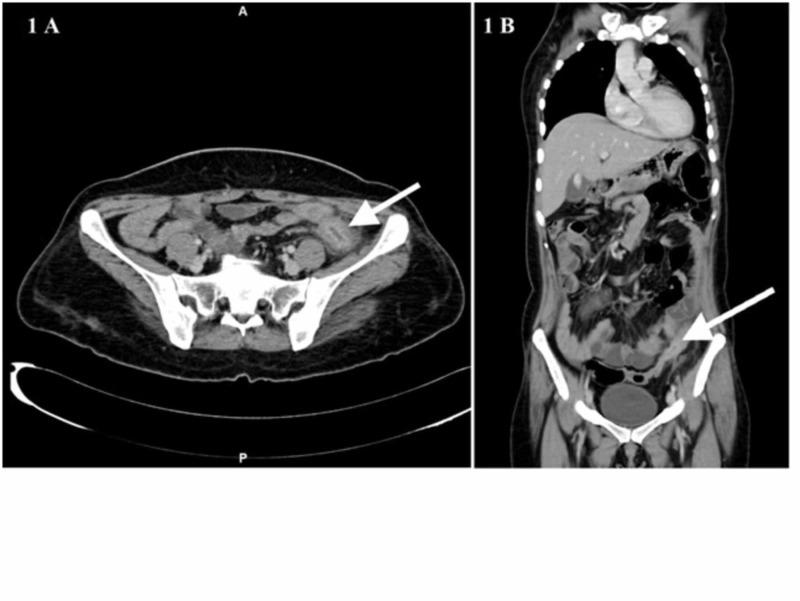

Inflammatory myofibroblastic tumors (IMFTs) are rare solid mesenchymal tumors frequently noted in children and young adults. It is characterized by variable clinicopathological and etiopathogenetic features. They are commonly reported in the lungs and occurrence in the colon is extremely rare. Here, we report a case of IMFT in the sigmoid colon confirmed histopathologically after surgical resection. A 40-year-old lady presented with abdominal pain, vomiting, and constipation for four days. On abdominal examination, there was tenderness in the left iliac fossa region with localized guarding. Contrast-enhanced computed tomography (CECT) showed a sigmoid colonic mass lesion with few enlarged perilesional lymph nodes. Colonoscopy demonstrated circumferential ulceration with irregular margin associated with luminal narrowing noted 55 cm from the anal verge and scope could not negotiate beyond, biopsies were taken. Later, the biopsy came as descriptive in nature. Hence, we proceeded for surgery and intra-operatively we have found there was circumferential thickening in the sigmoid colon for about size 8 cm of which was abutting the left lateral parietal wall. We have done sigmoid colon resection with adequate margins and postoperatively patient did well. Finally, the histopathology report suggested an IMFT sigmoid colon.

炎性肌纤维母细胞瘤(IMFTs)是罕见的实体间叶组织肿瘤,常见于儿童和年轻人。其具有多样的临床病理和病因发病学特征。它们通常在肺部被报道,而发生在结肠极为罕见。在此,我们报告一例经手术切除后经组织病理学确诊的乙状结肠IMFT病例。一名40岁女性因腹痛、呕吐和便秘4天就诊。腹部检查时,左髂窝区域有压痛并伴有局部肌紧张。增强计算机断层扫描(CECT)显示乙状结肠有一肿块病变,周围有少数肿大的淋巴结。结肠镜检查显示距肛缘55 cm处有边缘不规则的环形溃疡伴管腔狭窄,内镜无法通过,遂取活检。后来,活检结果为描述性。因此,我们进行了手术,术中发现乙状结肠有大约8 cm大小的环形增厚,与左侧顶壁相邻。我们进行了乙状结肠切除,切缘足够,术后患者恢复良好。最后,组织病理学报告提示为乙状结肠IMFT。